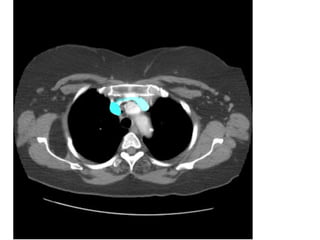

Hình chưa tiêm thuốc CTPA có tiêm

thuốc

Figure 10a. PE cấp không có triệu chứng ở bn nữ 87 tuổi.

(a) CT không cản quang thấy có vùng tăng đậm độ nhẹ bên trong động mạch

phổi

(P). (mũi tên).

(b) CTPA cho thấy PE cấp nhánh chính của động mạch phổi (P) và nhánh liên

thùy

1

3

của động mạch phổi (T).